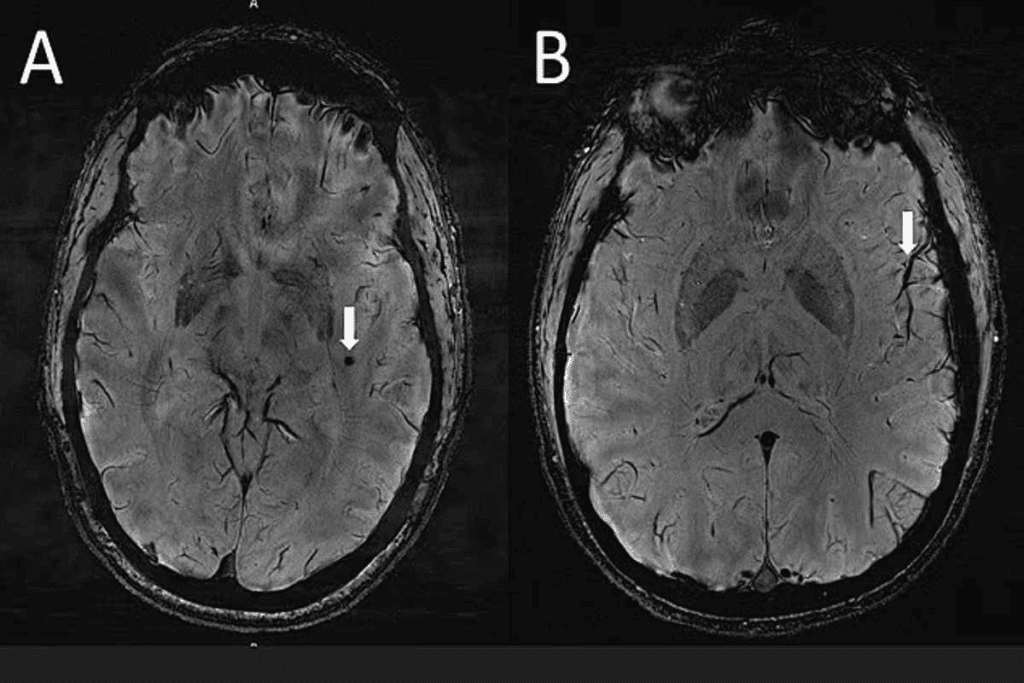

Imaging Techniques

Imaging techniques are vital for spotting brain lesions. The main ones are:

- Computed Tomography (CT) scans: CT scans give quick, detailed views of the brain. They help find lesions, bleeding, or other issues.

- Magnetic Resonance Imaging (MRI): MRI gives detailed images of the brain. It’s great for figuring out what kind of lesion it is, where it is, and how it affects the brain.